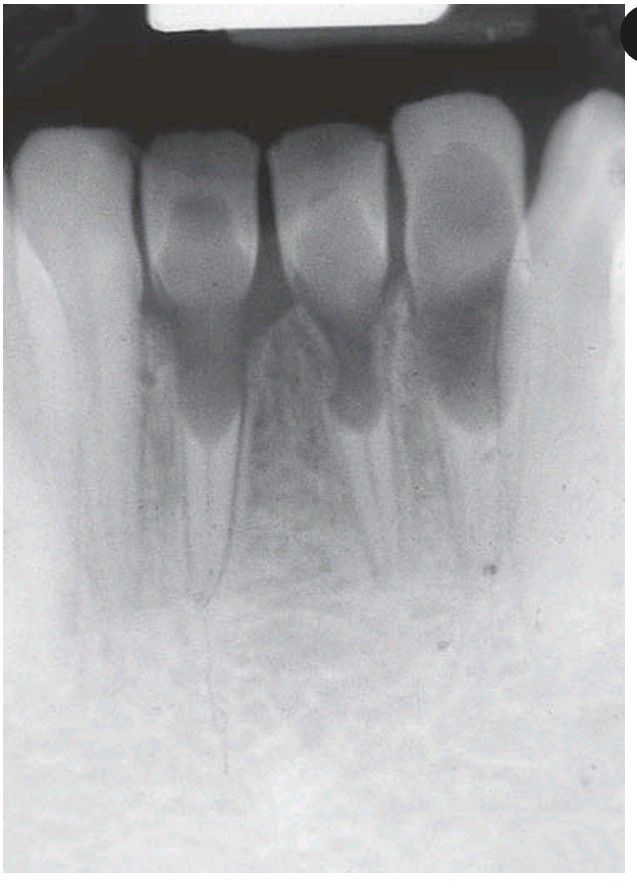

Internal resorption

Idiopathic internal resorption (‘pink spot’). In this unusually severe example, resorption has progressed into the roots of three lower incisors.